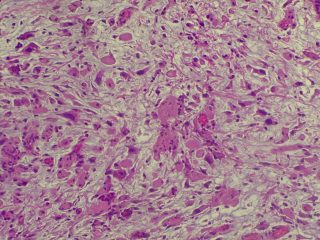

A vírus a csípést követően a bőrben elszaporodik, majd bekerül a véráramba, és a belső szervekben egy ismételt szaporodás után végül újra a bőrbe jut. Itt kialakulnak a klasszikus elváltozások, amelyek lényegében göbképződéssel járó gyulladásnak felelnek meg. A kórokozó hatására az irharétegben kialakulnak az ún. myxomasejtek (a myxomasejtek a mesenchyma-sejtekből kialakuló, nagy, sokszor nyúlványokkal rendelkező, módosult sejtek, amelyek tipikusak a myxomatosisban elhullott állatok irha rétegében) is. Az eddigi megfigyeléseink szerint a göbök a legintenzívebben a szemhéjakon, a száj körüli bőrképletekben és a genitáliákban jelennek meg, amelyet súlyosfokú vizenyő is kísér. Szövődményként gennyes jellegű orrgyulladás, bakokban tasakgyulladás és ivartól függetlenül kötőhártya-gyulladás is fellép, ami az érintett egyedek tájékozódási zavarával is jár. Mindennek eredményeként az állat lényegében képtelenné válik az életben maradásra: táplálkozása akadályozott, könnyű prédává válik a ragadozók számára és közútra tévedve gyakran a forgalom áldozatává válik.